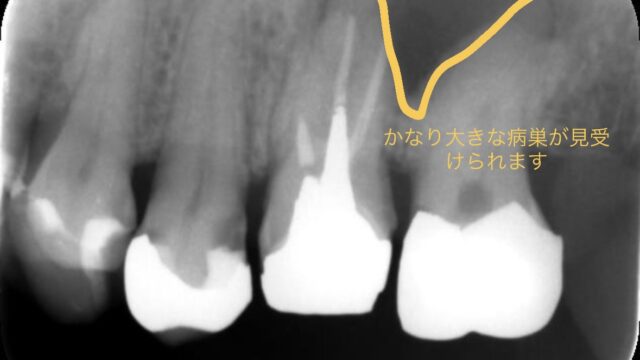

今回の根管治療開始から終了までのデンタルになります。

| 症状 | 左上6番目の歯を他院で根管治療後、被せ物を入れる前日に再び腫れた |